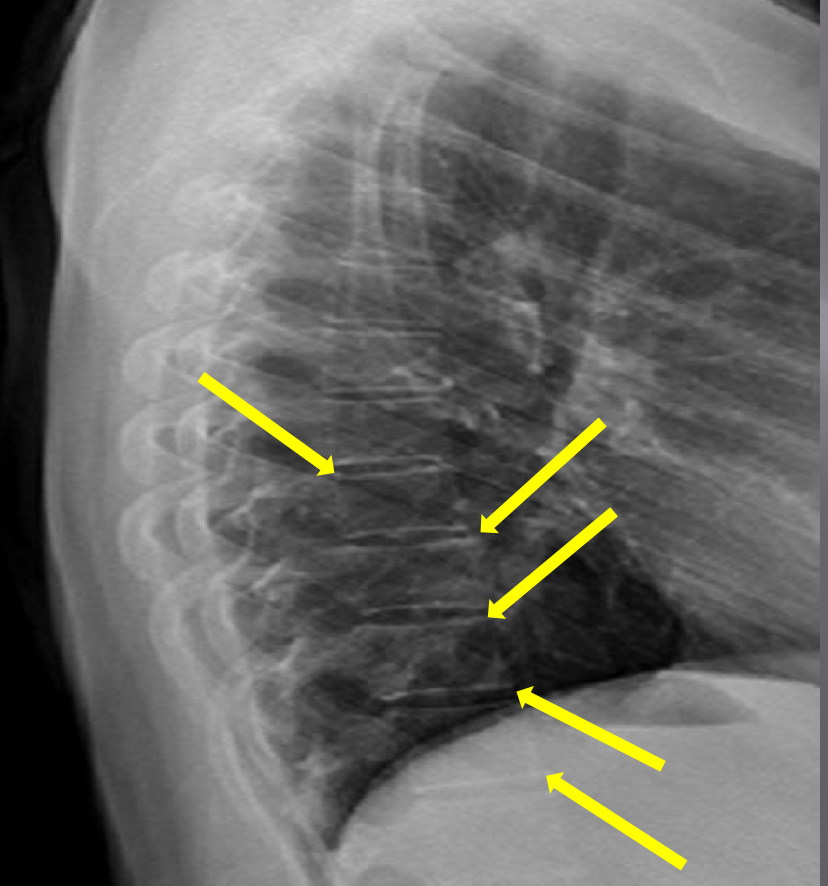

What view is this?

Lateral Thoracic

What is this?

Disc Spaces

What is this?

Endplate Tips